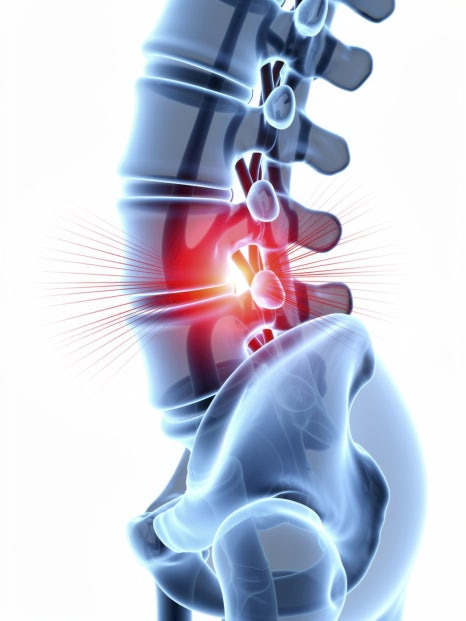

척추풍선확장술은 좁아지거나 압박된 척추 내부 공간을 확장하여 신경 주변의 여유 공간을 확보하고 구조적 안정성을 보완하는 시술입니다. 특수 카테터를 이용해 척추 내부에 접근한 뒤, 풍선을 활용해 공간을 확보하고 필요한 처치를 진행하는 방식으로 이루어집니다. 이 과정에서는 다음과 같은 의학적 개념이 함께 활용됩니다.

시술은 어떻게 진행될까요?

척추풍선확장술은 비교적 부담을 줄인 방식으로 진행되며, 단계는 다음과 같습니다.

1️ 국소마취 후 접근 부위 확보

2️ 특수 카테터를 이용해 목표 부위 진입

3️ 풍선을 이용해 내부 공간 확장

4️ 신경 주변 여유 공간 확보

5️ 필요한 보강 처치 후 마무리

이 과정은 영상장비를 통해 위치를 확인하면서 진행되기 때문에 정확한 부위 접근이 중요한 요소로 작용합니다.